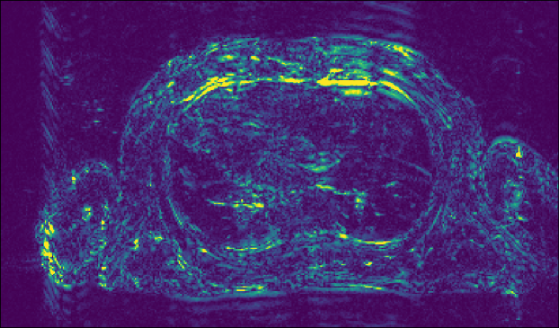

Figure 3 shows an example of cine images reconstructed with the methods reported. We see that our proposed approach accurately removes undersampling artifacts and clearly outperforms baseline comparison methods. Table 1 lists the metrics on the (cropped) CMRxRecon validation dataset as reported by the public leaderboard.

| Coilwise U-Net | E2E-VarNet | Proposed | GT / RSS |